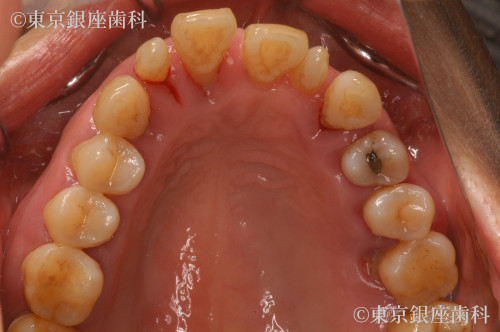

全顎的な重度歯周病による動揺、歯列崩壊をワンデイインプラントで改善した症例

全体的に歯がぐらつき出血し、何本か抜けてしまった。日に日に悪くなっている。他院で総入れ歯しかないと言われた。

全顎的に歯周病が進行し早急に抜歯が必要な歯が何本もあった。咬合改善、審美回復も望まれていたため全ての歯を抜歯し上下ワンデイインプラントを計画した。その際、左上顎洞部分の骨が薄いことから、人工骨を用いて骨量を増やしインプラントの安定を図るサイナスリフトも同時に行うこととした。